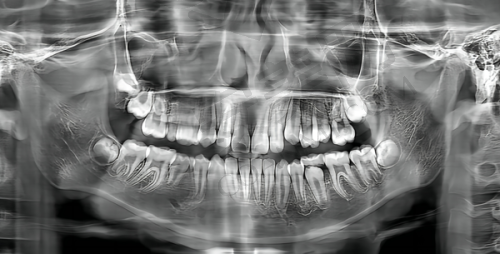

第一次到盐城中喜口腔医院,给我的第一印象就是环境特别干净整洁,医护人员也都特别热情。我到医院后,前台工作人员特别快就帮我安排了医生。医生先是详细询问了我的病史和牙齿情况,然后带我去做了一系列的检查,包括口腔X光片、CT扫描等。通过这些检查,医生全方面了解了我的牙槽骨状况、牙齿缺失情况以及周围组织的健康状况。

检查结束后,医生根据我的检查结果为我制定了个性化的种植牙方案。医生耐心地向我解释了方案的具体内容,包括种植体的选择、种植的步骤、手术的风险等。我也向医生提出了一些疑问,医生都一一解答,让我对种植牙有了更清晰的认识。在和医生充分沟通后,我决定按照医生制定的方案进行种植牙手术。